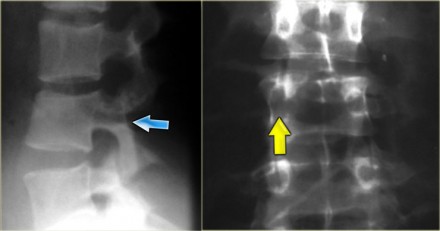

Chance fracture

On the left images of a 21-year-old female who presented after sustaining a seatbelt type injury.

She had an exploratory laparotomy for repair of a ruptured duodenum.

There was no neurologic deficit.

First study the images, then continue reading.

What we see is a classic example of a chance fracture,

which is a three column injury with a horizontal orientation of the

fracture.

Continue with the CT-images.

What is unique about the Chance fracture is the

horizontal orientation, which is nicely demonstrated on the sagittal

reconstructions on the left.

Continue with the coronal reconstructions.

Also on the coronal reconstructions we can see the horizontal orientation of the fracture.

On the left another example of a Chance fracture.

Chance fracture (3)

On the left a Chance variant.

This is a pure ligamentous injury, which is analogous to bilateral

interfacet dislocation, which is also a pure ligamentous injury.

There is rupture of the interspinous ligament, dislocation of the facet joints and a horizontal rupture of the disc.

Pure ligamentous and combined osseous / ligamentous variants have an increased risk of instability compared to the osseus type.

Always look for a split of the posterior elements, disc widening or widening of the spinous processes and facets.